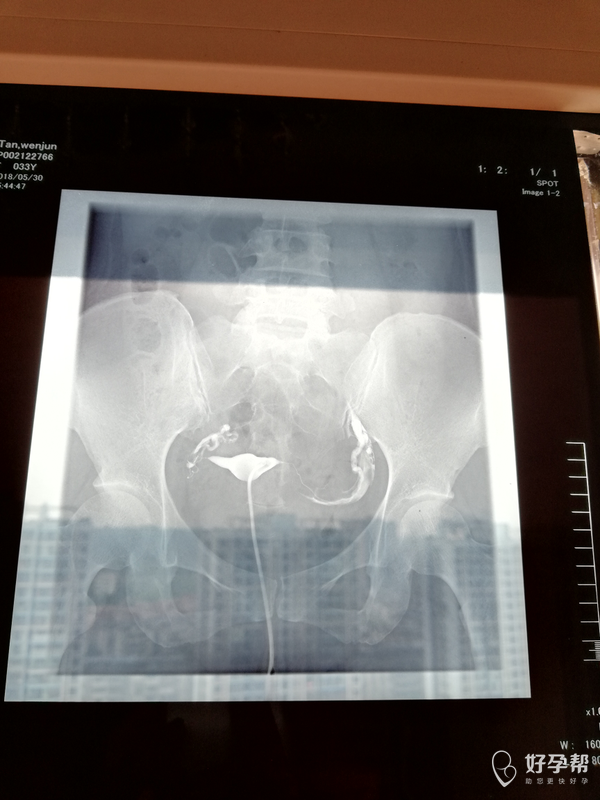

输卵管造影,双侧走行迂曲、僵硬,右侧末端弥散欠佳。